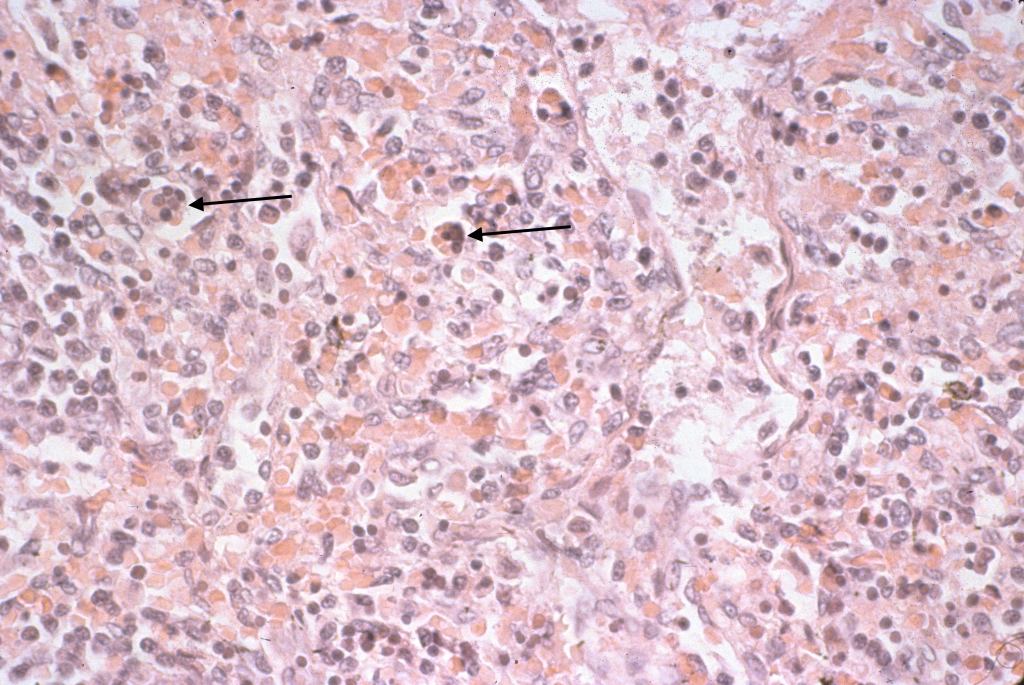

The RE system may also show phagocytosis of targeted white blood cells, hemophagocytic lymphohistiocytosis (HLH) (Fig 8).

Fig 8: The splenic sinuses show phagocytosis of red and white blood cells (arrows). The infant was an intrapartum death at 22 weeks of gestation having hydrops of undetermined etiology. There was massive hepatomegaly with similar hemophagocytic lymphohistiocytosis (HLH) and increased erythropoiesis. The skin had numerous small capillary proliferations in the dermis. Primary HLH could not be excluded as genetic studies were not available. (40x, H&E)